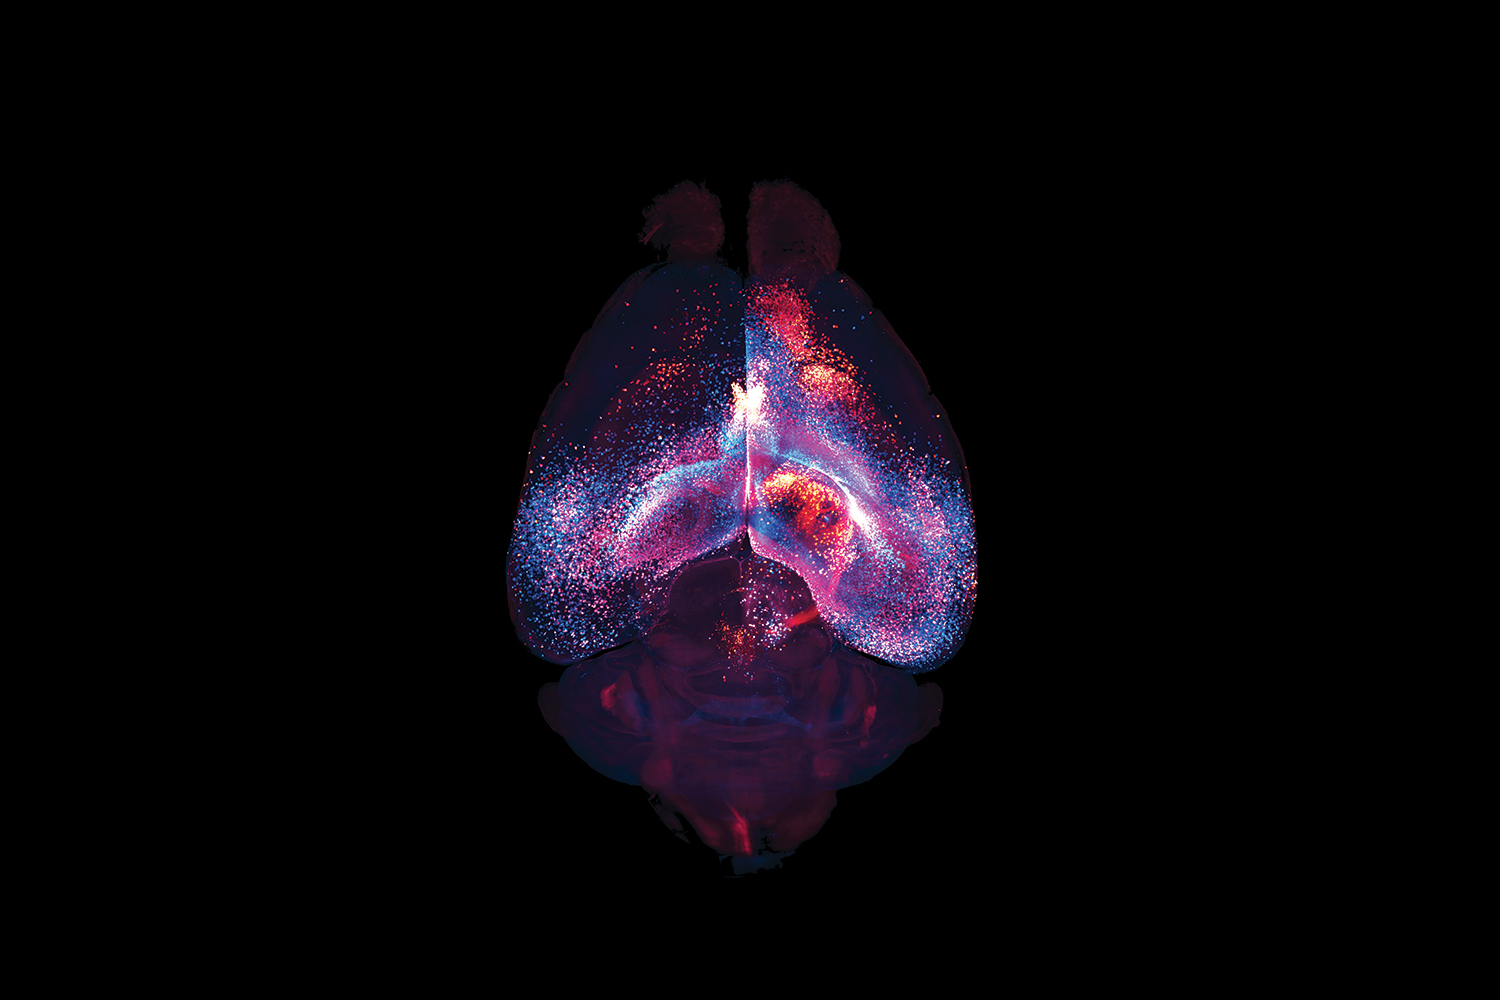

To Discover